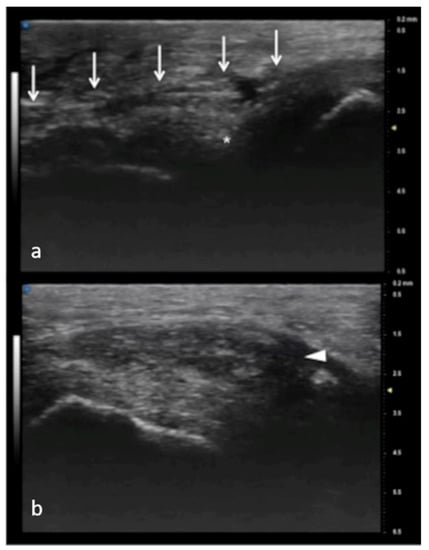

Figure 4.

Juvenile idiopathic arthritis (JIA). UHFUS gives clear details of pathological findings in pediatric patients with JIA. In (a), articular effusion (E) at the level of the metacarpal–phalangeal joint (MET-PP). In (b), osseous erosions at the level of the metacarpal head (white arrows).

Figure 5.

Juvenile idiopathic arthritis. UHFUS gives clear details of pathological findings in pediatric patients with JIA. In (a), articular effusion (E) at the level of wrist and enthesophyte (white arrow). Thickened capsule (arrowheads) in (a) presenting with an increased Doppler signal (white square) in (b).